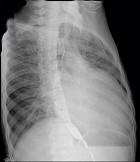

问题 56岁男性患者,劳累后心慌气促10余年,近来自觉症状加重。临床听诊,心尖区有舒张期隆隆样杂音,行胸部X检查,如图所示,你认为下列描述正确的是 ( )

选项 A、考虑三尖瓣狭窄 B、右前斜位示左心房增大,心后上缘后突压迫冲钡食管 C、左前斜位示心影向后下方突出 D、考虑二尖瓣狭窄

答案 BCD